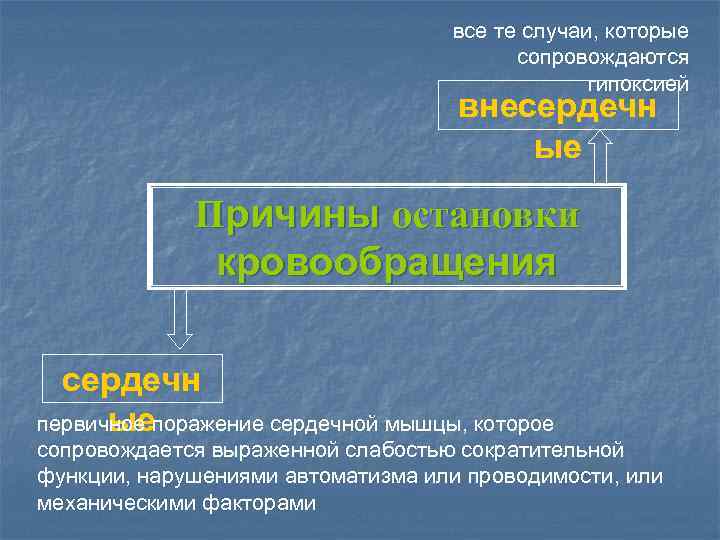

все те случаи, которые сопровождаются гипоксией внесердечн ые Причины остановки кровообращения сердечн первичное поражение сердечной мышцы, которое ые сопровождается выраженной слабостью сократительной функции, нарушениями автоматизма или проводимости, или механическими факторами